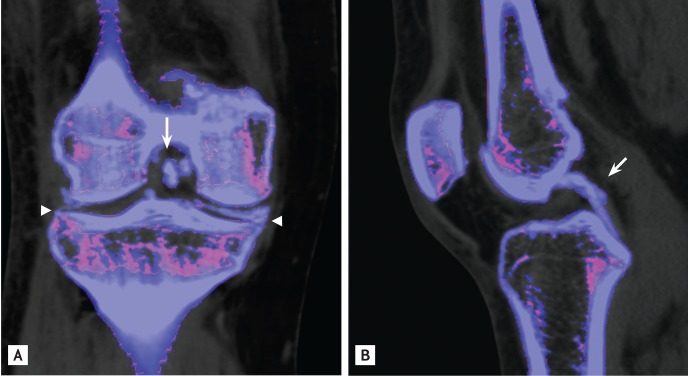

Figure 1

Plain radiographs show multiple calcifications in both (A) medial and lateral menisci (arrows), and (B) femoral condylar cartilage (arrowhead).

A 52-year-old woman presented with painful swelling in both knees for 7 days. Physical examination identified marked swelling and tenderness in both knee joints that she reported to have recurred for the past 6 years. Laboratory tests determined the erythrocyte sedimentation rate to be 107 mm/hr, C-reactive protein as 25.55 mg/dL, and serum uric acid levels as 4.1 mg/dL. Calcium pyrophosphate dihydrate (CPPD) crystals were found on polarized light microscopy examination of knee joint synovial fluid. Cultures identified no microorganisms. Plain radiography of the right knee revealed multiple calcifications in the medial and lateral menisci and the femoral condylar cartilage (Fig. 1). Dual-energy computed tomography (DECT), which differentiates monosodium urate (color-coded in green) from calcium (color-coded in blue), revealed multiple calcium depositions in the anterior and posterior cruciate ligaments, as well as in both menisci and the femoral condylar cartilage (Fig. 2). The patient was diagnosed as having CPPD crystal deposition disease of both knee joints. Intra-articular injection of triamcinolone effectively relieved her pain.